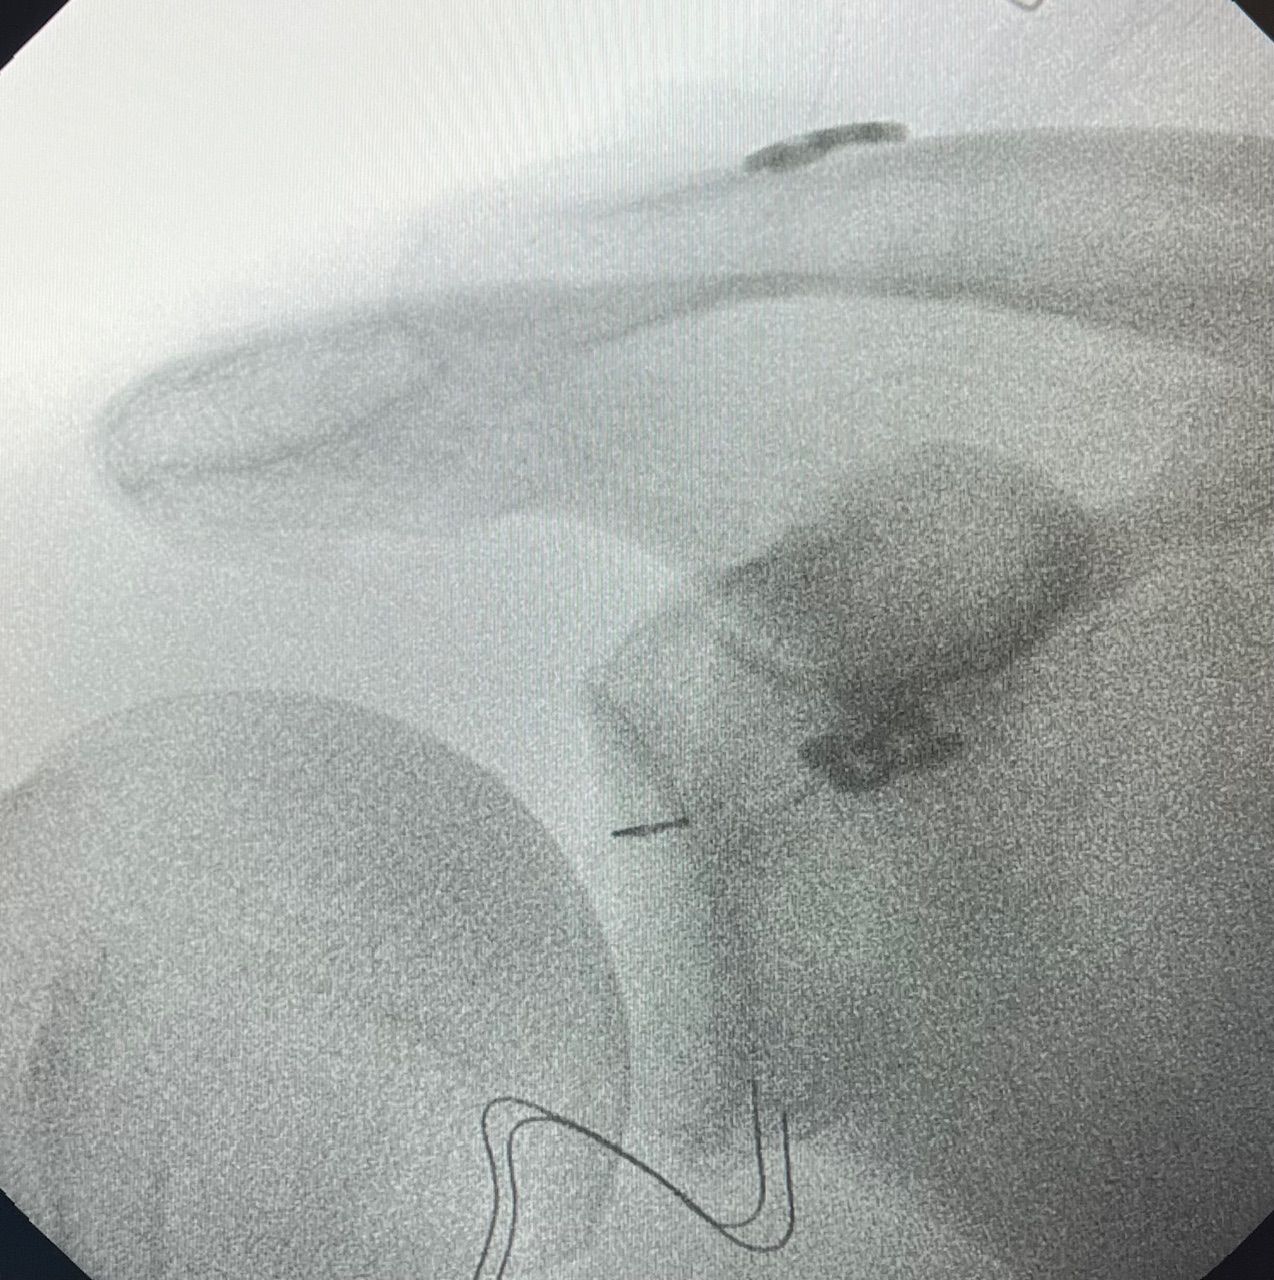

Fotos y vídeos